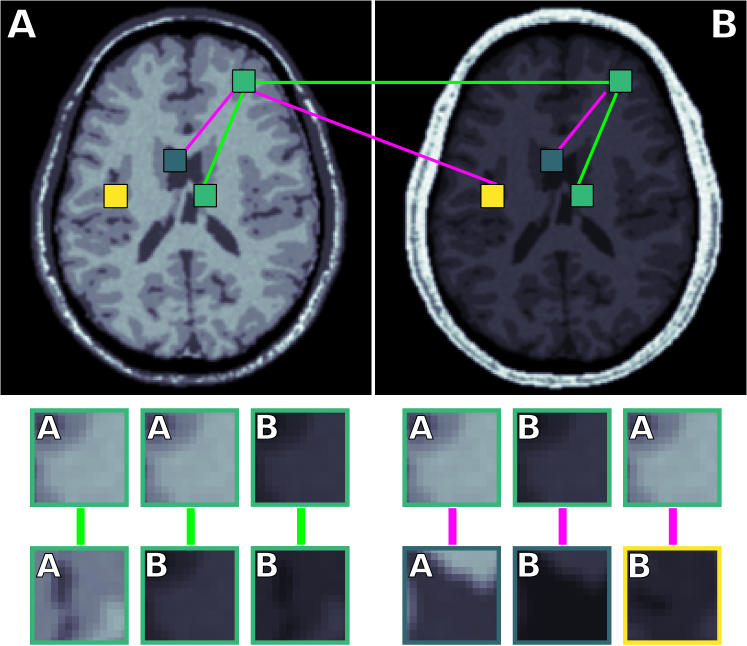

Figure 1 illustrates the process of selecting pairs of patches from different scanners. Consider a medical image from scanner A and scanner B, with 2 GM patches (green), 1 WM patch (yellow) and 1 CSF patch (blue) for each image. Using these patches we can generate the following pairs: a GM patch from A with another GM patch from A , a GM patch from A with a GM patch from B , a GM patch from B with another GM patch from B , a GM patch from A with a CSF patch from A , a GM patch from B with a WM patch from B , and a GM patch from B with a CSF patch from B . The bottom of the image shows examples of these 6 pairs of patches.

The proposed network works as follows. Suppose that we have scans that are acquired in two different ways (A and B). Possible differences can be in field strength, scanner vendor, acquisition protocol, and so on. A tissue patch, for example gray matter, is selected from both scans A and B. The aim is to teach the network that both these patches are gray matter regardless of their acquisition variation. Therefore, we use a loss function that expresses that in the mrai representation, pairs of samples from the same tissue but from different scanners should be as similar as possible. However, that expression alone would cause all samples to be mapped to a single point and would destroy variation between tissues. To balance out the action of pulling pairs marked as similar together, it is necessary to push other pairs apart [23]. Since we want to maintain the relevant variation between tissues, we additionally express that in the mrai representation, pairs from different tissues should retain their dissimilarity. The loss function is described in section 2.1. Section 2.2 describes how pairs of samples are labeled as similar or dissimilar. The Siamese neural network that is used to learn the mrai representation is described in section 2.3. The network consists of two pipelines with shared weights and a Siamese loss layer that acts on the output layer of the two pipelines (mrai representation).

2.2 Labeling pairs as similar or dissimilar

As described above, suppose we have two medical images from two different scanners; A and B. Assume that we have sufficient manual segmentations (labeled voxels) on scans from scanner A, to train a supervised classifier, but a very limited amount of labels from scanner B, for example labeled voxel per tissue for subject. The data from scanner A will be referred to as the source set, and the data from scanner B as the target set. Let be the set of tissue labels. The set of patches extracted from Scanner A is denoted , and the set from scanner B is denoted , with specifying the sample’s tissue. Given these two sets of patches, we form sets of similar and dissimilar pairs, with a similarity label . The following pairs are labeled as similar () and therefore will be pulled closer together: